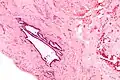

High magnification micrograph of endosalpingiosis, showing the characteristic cystic spaces lined by a simple epithelium with cilia. H&E stain. | |

It is characterized by cysts with tubal-type epithelium (e.g. ciliated epithelium) surrounded by a fibrous stroma. It is not often associated with hemorrhage.